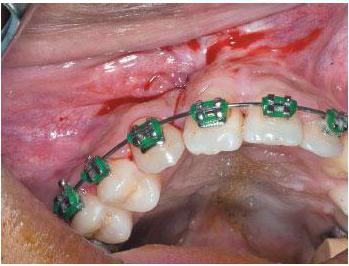

У деяких випадках відросток є вузьким горбистим і нерівним. При цьому використовується біоматеріал розміщується одночасно з кісткової поверхні і над нею. За рахунок цього лікар може надати кістки необхідну форму. Під час корекції може також знадобитися розсічення окістя і надрізання слизової оболонки відростка. Після цього лікар готує кістка (надає їй потрібну форму), а потім ставить використовується для імплантації матеріал. Краї окістя зшиваються, щоб вийшла більш правильна форма. Вся процедура здійснюється під місцевим наркозом. Крім того, лікар може видалити надлишки, тяжі, нависаючі краї. Реконструкція відбудеться без ускладнень, якщо до і після операції хворий буде дотримуватися всіх рекомендацій свого лікаря.

- Виконання корекції всередині кістки. Однак лікар не може відразу приступити до пластики, оскільки спочатку він повинен зробити вертикальну остеотомію, а також транспозицію кісткових стінок.

- Здійснення реконструкції шляхом розрізання гребеня відростка.

- Також пластику може відбуватися на поверхні кісткового ската. Робиться вона внакладку.

- Остеотомія. Її виконує лікар-хірург шляхом надломления стінки. Отримане простір в результаті операції заповнюється спеціальним біоматеріалом.